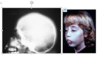

What is this radiographic finding?

Periapical Cysts

►Would need to test both teeth for vitality.

What is this radiographic finding?

Periapical Cyst